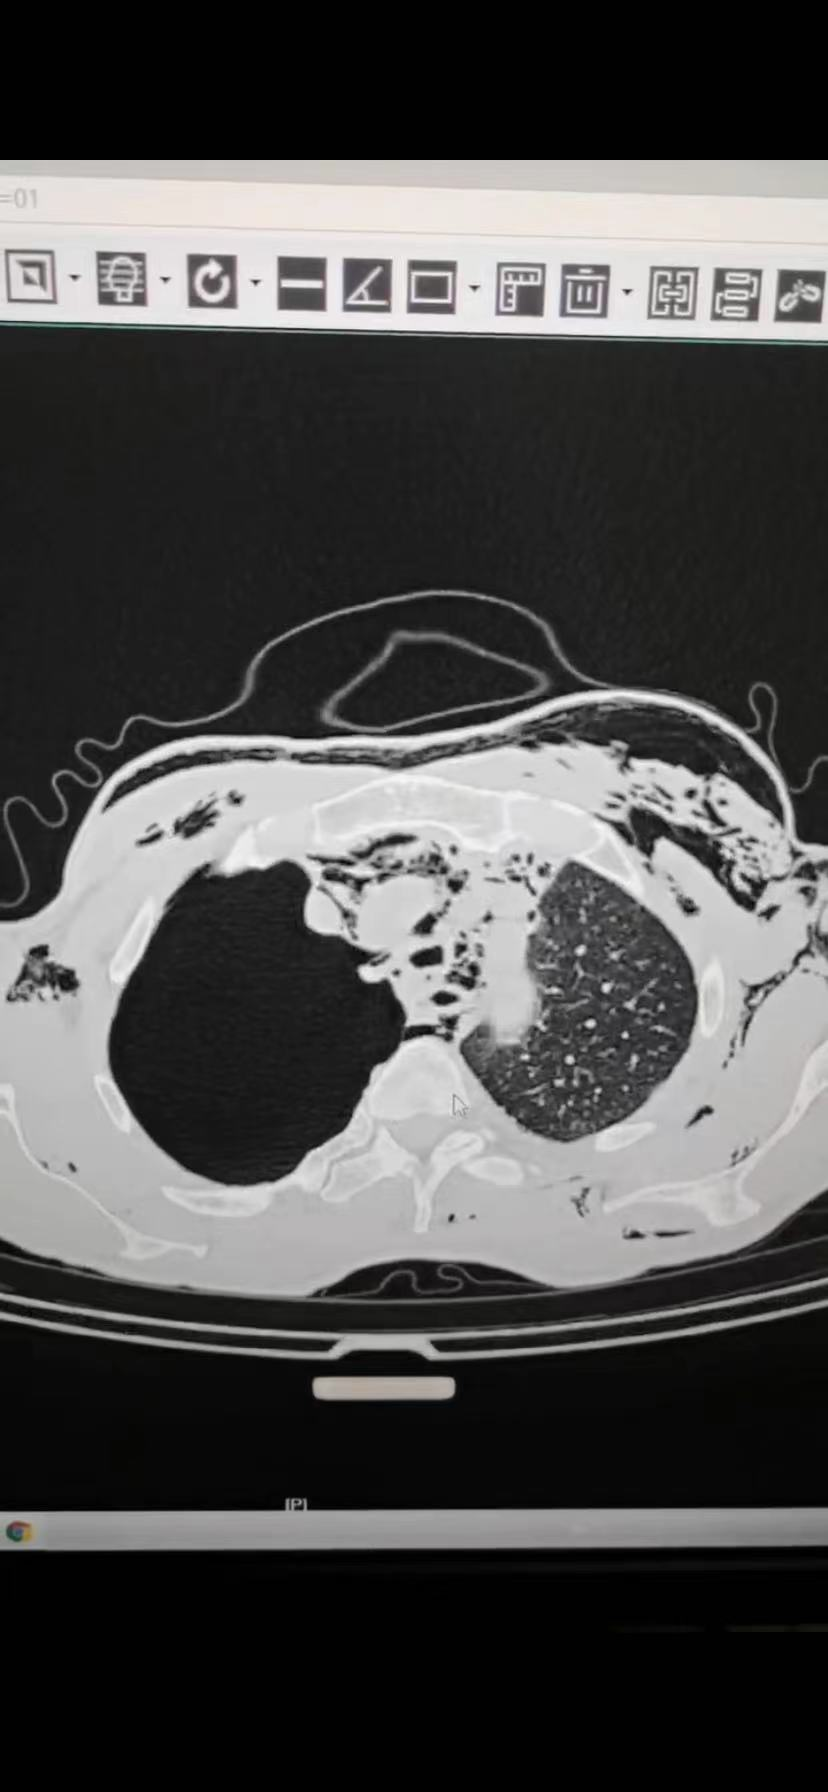

绿色通道高效救治,多学科联动配合 胸心外科成功救治一例外伤性气管破裂

2023-05-29 16:24